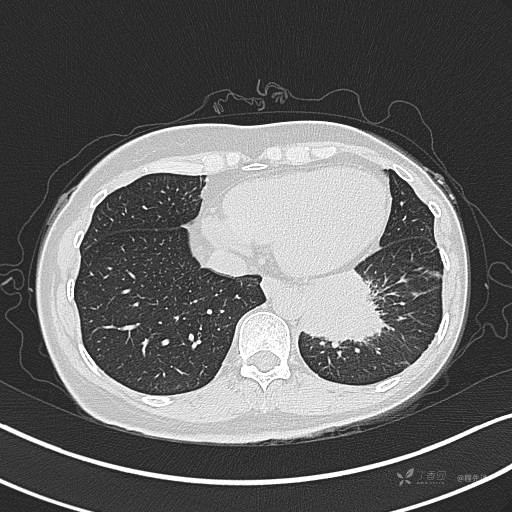

CT平扫

肺窗